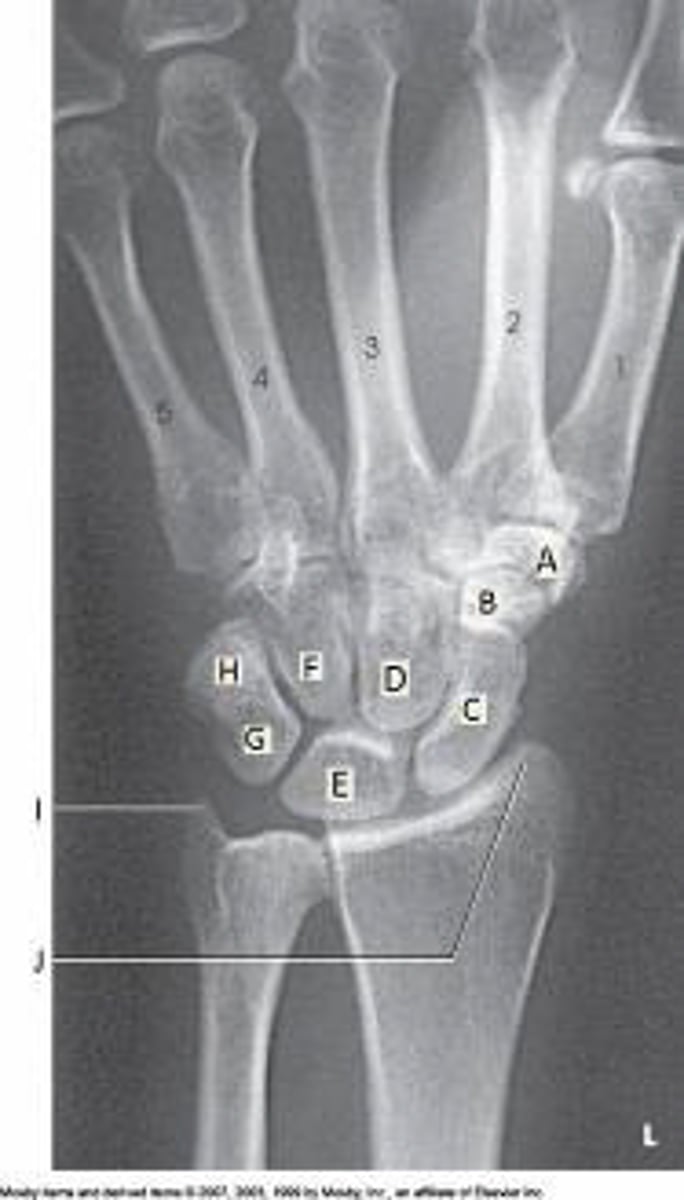

Lunate

C

Letter H in the image below labels the:

cuboid